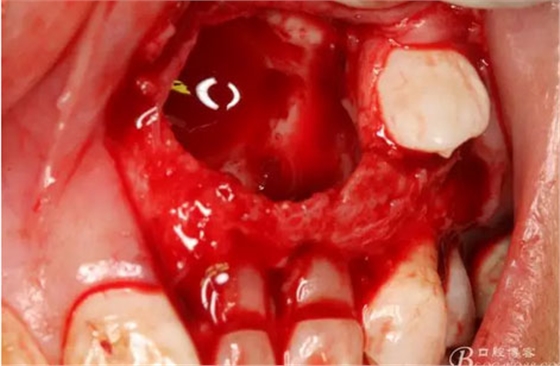

圖18.摘除囊腫后遺留的巨大骨腔

圖19.生理鹽水沖洗骨腔,修整骨腔表面

圖21.術中拍全景片,看是否有牙瘤殘留,發(fā)現(xiàn)左側(cè)乳Ⅱ根尖區(qū)還有少量致密鈣化物,建議拔除左側(cè)乳Ⅱ、,患者要求保留兩個乳牙。經(jīng)協(xié)商,遺留極少量鈣化物,不影響整體愈合。通過骨腔探查,發(fā)現(xiàn)左側(cè)乳Ⅱ、Ⅲ根尖區(qū)未破壞,骨壁尚完整。同意遺留部分鈣化物。有點缺憾,為了保留乳牙和患者的美觀及功能。定期觀察遺留部分的發(fā)展變化

圖22.為了保留兩顆乳牙,不再去除遺留部分鈣化物,遂膠原蛋白海綿填塞兩個缺損骨腔。